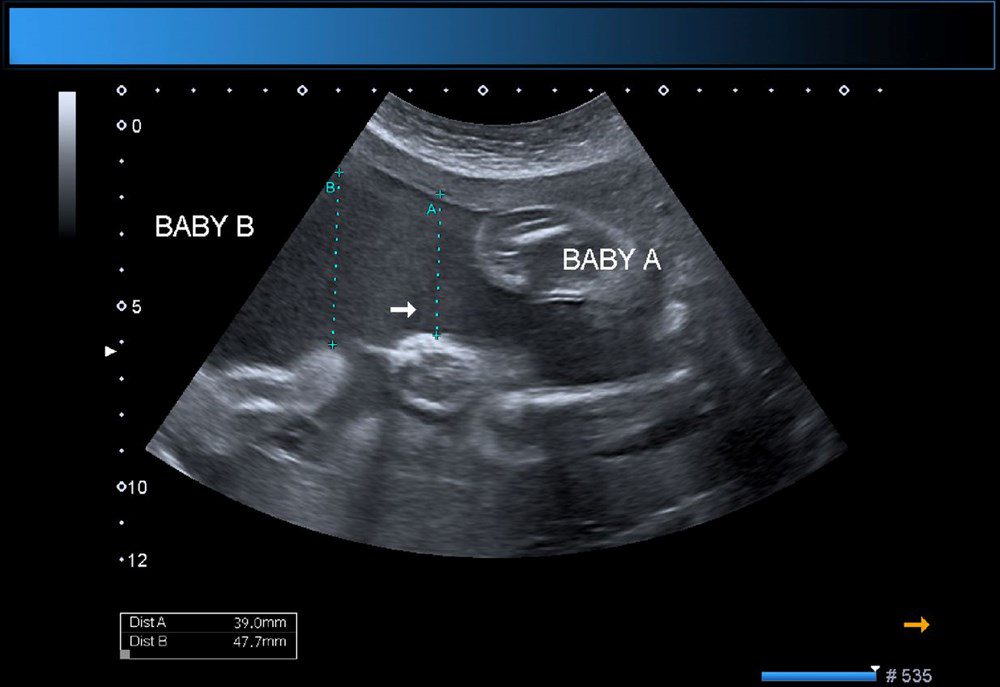

Yeni bir araştırmaya göre, Çin’de doktorlar bir yaşındaki bir çocuğun beyninde ‘doğmamış ikizinin fetüsünü’ buldu. Neurology dergisinde yayınlanan çalışmada, çocuğun motor fonksiyonlarında sorunlar yaşaması ve kafasının büyümesi üzerine ebeveynleri tarafından hastaneye getirildiği ortaya çıktı. Şangay’daki doktorlar, doğmamış ikizin fetüsünün çocuğun beyninde geliştiğini tespit etti. Çalışmanın yazarları, “Motor becerilerinde gecikmesi ve genişlemiş baş çevresi olan 1 yaşındaki bir kız çocuğunda malforme olmuş monokoryonik diamniyotik ikiz olan intraventriküler fetüs içinde fetüs (fetus-in-fetu) tespit edildi.” denildi.